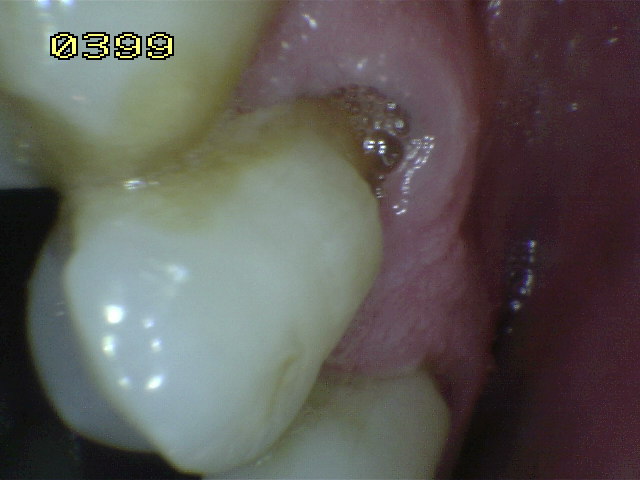

Código 1:

Hay una zona

claramente delimitada

en la

superficie de la raíz

o en la unión

cemento-esmalte

(UCE)

que es de color (claro,

oscuro, marrón y negro),

pero no hay

cavidad

presente,

(pérdida del

contorno anatómico

menor a

0,5

mm)

detectable con sonda periodontal. |